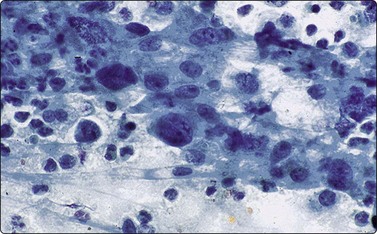

Seminomas and dysgerminomas yield highly cellular aspirates composed of both loose clusters and individually scattered round tumor cells with round nuclei containing finely granular chromatin and a prominent single nucleolus (Fig. 17.28).96 A moderate to abundant amount of cytoplasm can be present and PAS-positive cytoplasmic vacuoles are often seen. The smear background contains chronic inflammatory cells with occasional granulomas. Due to the spillage of the glycogen-rich cytoplasm, a characteristic ‘tigroid’ background can be appreciated and serves as a useful diagnostic clue (Fig. 17.28). In contrast, embryonal carcinoma consists of large three-dimensional clusters of tumor cells with indistinct cell boundaries. Papillary and glandular clusters may contain delicate branching blood vessels. The neoplastic cells show pleomorphism with coarsely granular chromatin and multiple prominent nucleoli (Fig. 17.29). As previously mentioned, FNA biopsy of the testicle has also been used to document relapse of acute lymphoblastic leukemia in children and could be considered as an alternative procedure to surgical biopsy.71,76,99

image

Fig. 17.29 Embryonal carcinoma

Numerous pleomorphic neoplastic cells with coarsely clumped chromatin, multiple nucleoli, and variable amounts of granular cytoplasm (Diff-Quik, ×400).